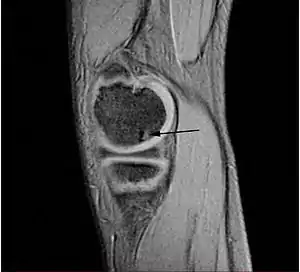

Osteocondritis disecante (a menudo abreviado TOC o DO) es un trastorno común en el que se forman grietas en el cartílago articular y el hueso subyacente subcondral. El TOC es una complicación de la necrosis avascular que se producen en el hueso subcondral.[1] Esta necrosis avascular priva de sangre a los huesos; el tejido afectado muere y se reabsorbe. El hueso subcondral se pierde, el cartílago articular anterior se separa del hueso y es más propenso a los daños, como la fragmentación (disección) de los cartílagos y huesos, y la libre circulación de estos fragmentos osteocondrales en el espacio articular, causando más dolor y daño.[2][3][4]

TOC generalmente causa dolor e hinchazón de la articulación afectada y bloqueos de la circulación. El examen físico revela un derrame, sensibilidad y crepitación. El TOC puede ser difícil de diagnosticar porque los síntomas parecen a otras enfermedades. Sin embargo, la enfermedad puede ser confirmado por los rayos X, la tomografía computarizada (CT) o imágenes de resonancia magnética (MRI) explora. OCD está clasificada por estas técnicas de imagen, o por artroscopia de la articulación, y representada en las fases (I, II, III y IV), de la progresión de la enfermedad. Tras el diagnóstico de la enfermedad puede ser tratado, dependiendo de su gravedad, por la reparación del cartílago.[5][6] El tratamiento no quirúrgico rara vez es una opción, ya que el cartílago tiene una limitada capacidad para curar. Como resultado, incluso moderados casos requieren algún tipo de cirugía. Cuando sea posible, no el tipo de gestión como protegidas peso (parcial o no del peso) y la inmovilización se utilizan. El tratamiento quirúrgico varía ampliamente e incluye la perforación de lesiones artroscópicas intactas, la seguridad de las lesiones del cartílago solapa con clavijas o tornillos, la perforación y la sustitución de cartílago enchufes, trasplante de células madre, y reemplazo de articulaciones.

TOC está clasificado por la progresión de la enfermedad en etapas. Existen dos clasificaciones de etapas más utilizados, uno es determinada por resonancia magnética de imágenes de diagnóstico, mientras que la otra está determinada por artroscopia. Sin embargo, ambas puestas en escena representan las condiciones patológicas asociadas con la progresión natural OCD.

Aunque la clasificación artroscópica de las lesiones osteocondrales se considera estándar, la puesta en escena Anderson RM es la principal forma de clasificación usado en este artículo.[7] Etapas I y II son lesiones estables. Etapas III y IV se describen las lesiones inestables en el que una lesión del cartílago ha permitido que el líquido sinovial entre el fragmento y el hueso.